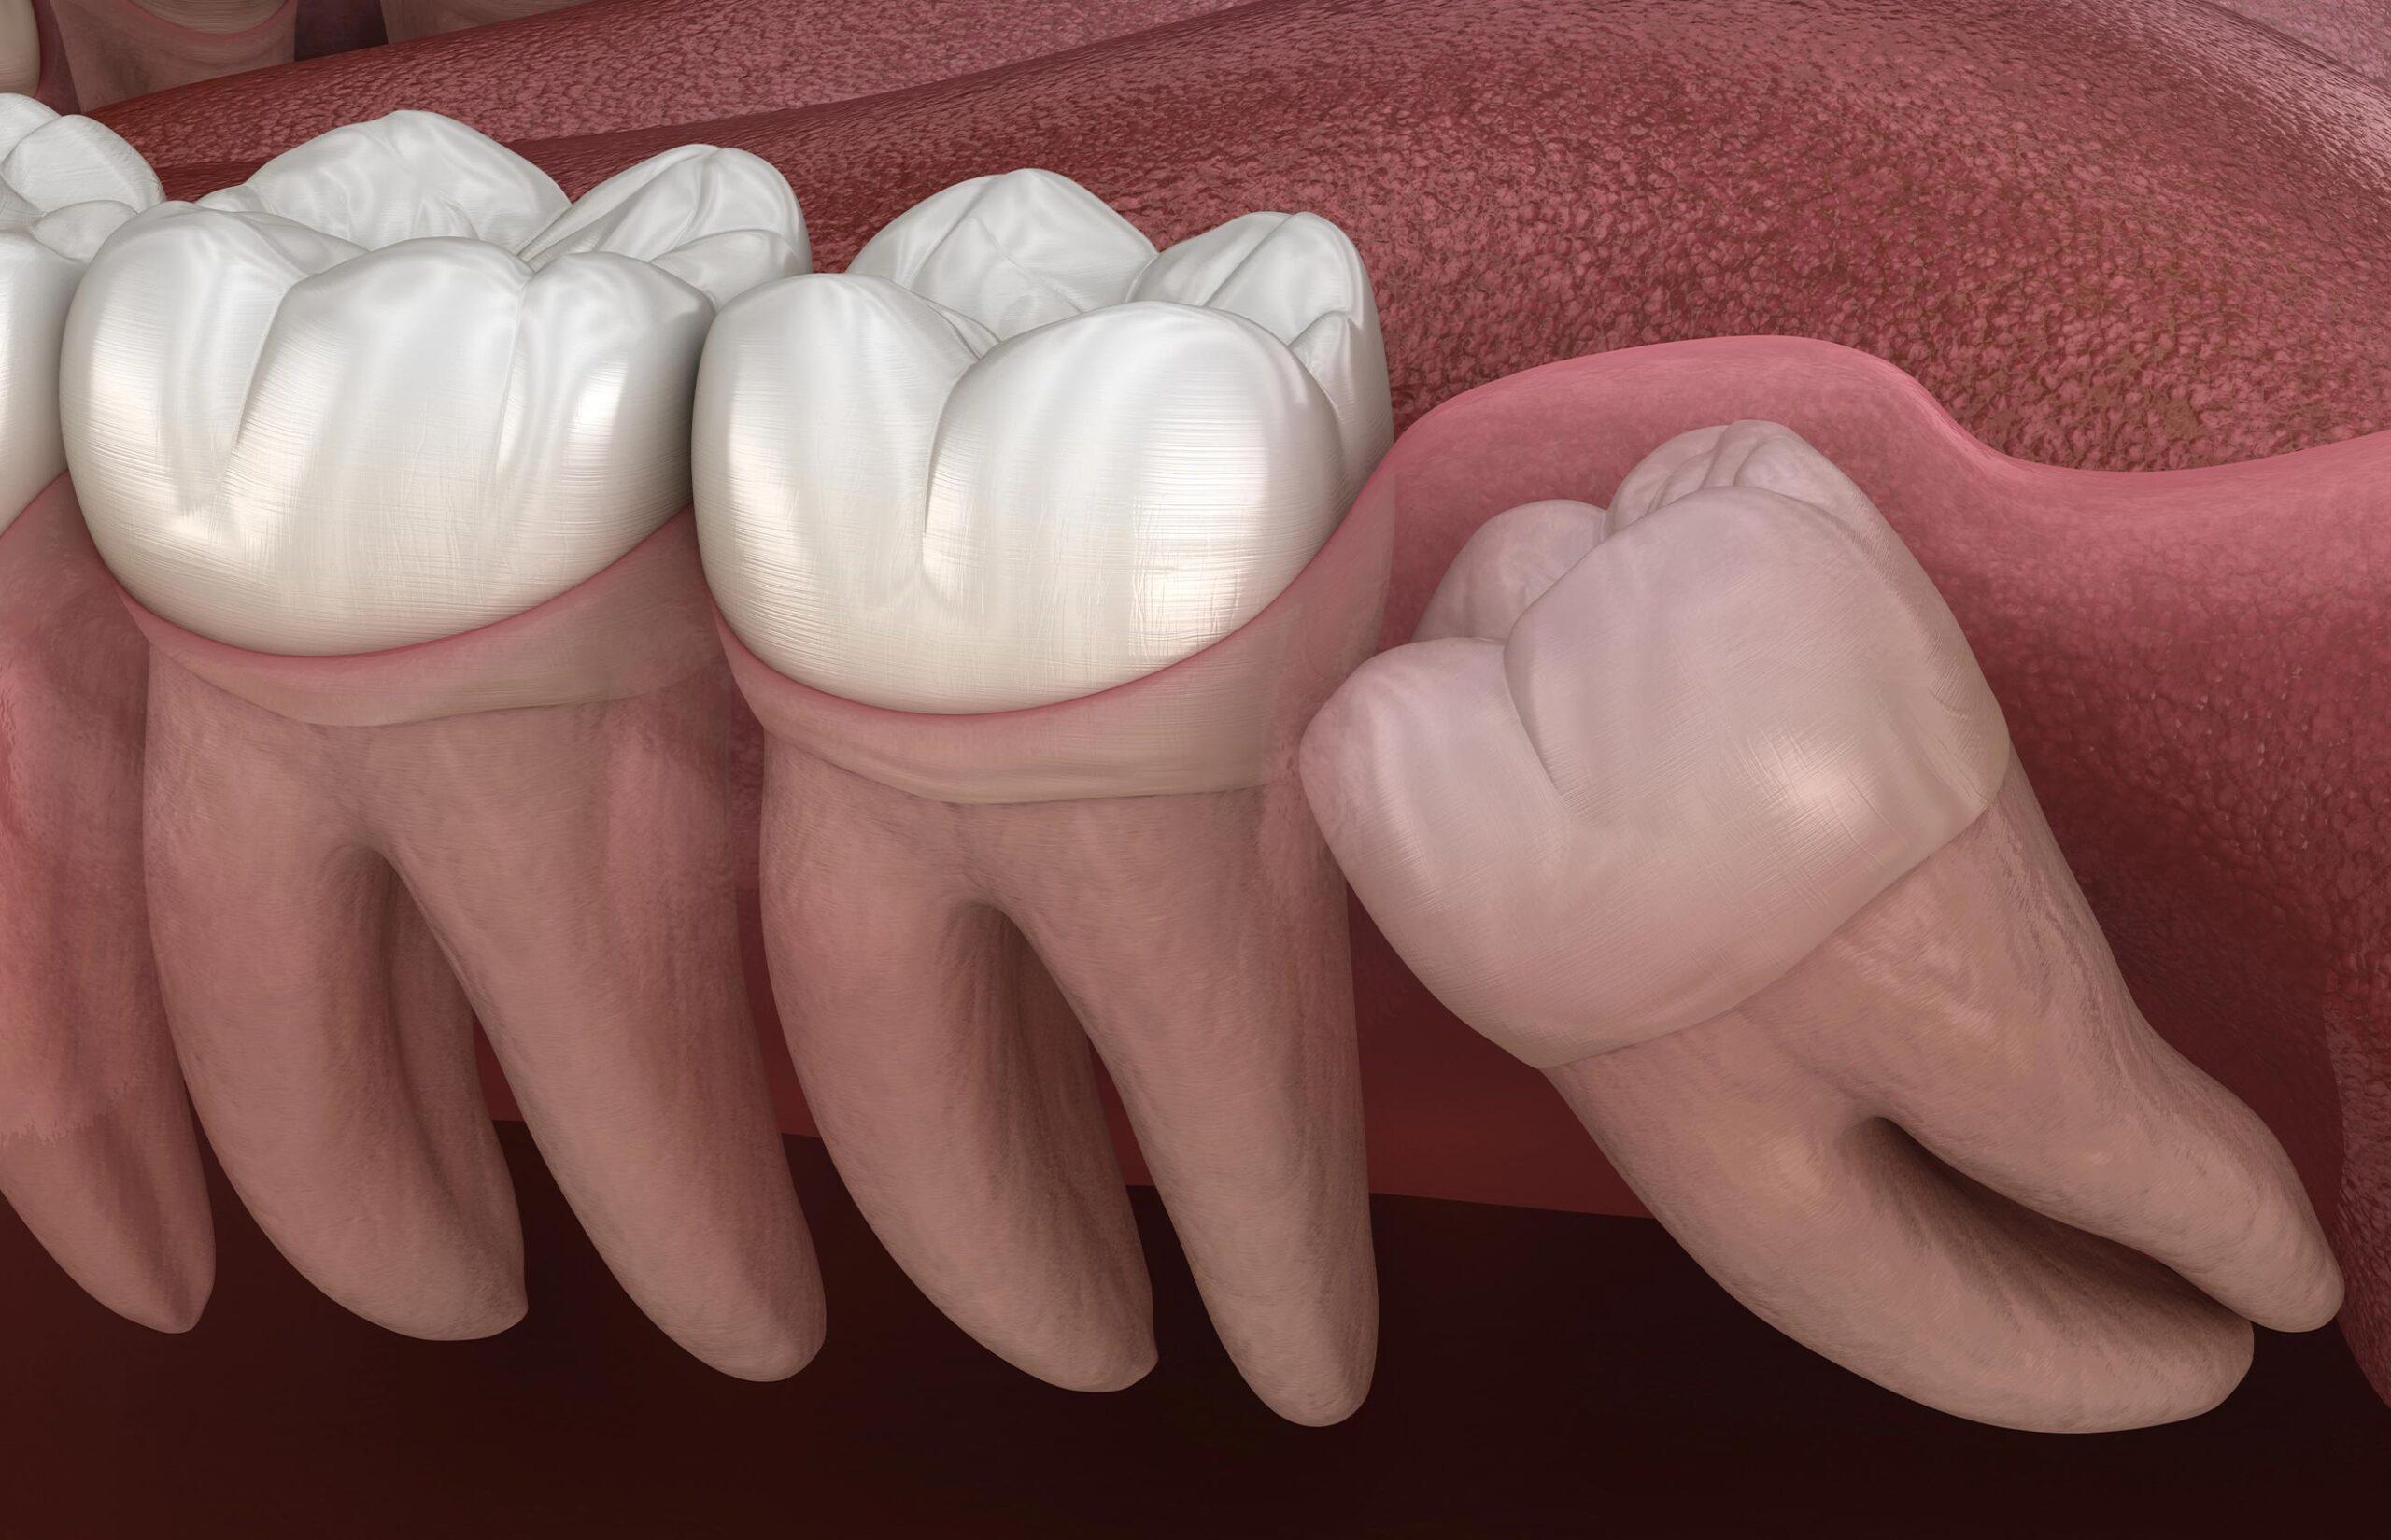

• Growing at an angle, placing pressure on neighbouring teeth or contributing to crowding

• Impacted beneath the gums or bone, which may lead to swelling, discomfort, or infection